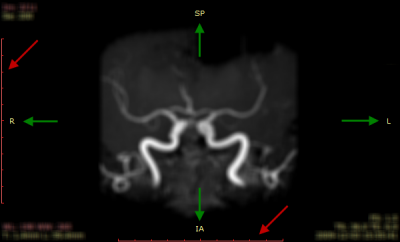

如果 DICOM 图像包含比例信息(像素间距),面板左侧和底部将显示两条带 1 cm 刻度的 10 cm 标尺(红色箭头所示)。

如果 DICOM 图像包含患者空间方位信息,每个面板边缘的中央将显示代表患者方位的字母(绿色箭头所示):

- A – 前(Anterior)

- P – 后(Posterior)

- L – 左(Left)

- R – 右(Right)

- S – 上(Superior)

- I – 下(Inferior)